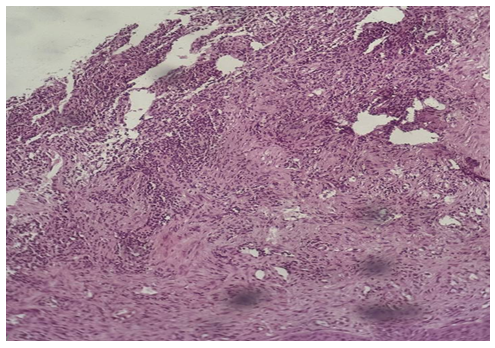

| Picture 3. Surgically resected specimen of salivary gland tumor. Histological appearance of monomorphic adenoma, localized in the left submandibular gland (1 case; No. 1101). The lesion shows uniform epithelial cell proliferation arranged in solid and trabecular patterns with sharp demarcation from the surrounding tissue (H&E stain) |

Morphological description: The histological section demonstrates infiltrative tumor growth with dense sheets of atypical epithelial cells. Cells display pleomorphism, irregular nuclear contours, hyperchromasia, and scant cytoplasm. The stroma is fibrous, with focal desmoplastic reaction. No signs of glandular or squamous differentiation are present, which is consistent with the diagnosis of undifferentiated carcinoma of the mandible. Figure 2. Undifferentiated carcinoma of the mandible showing sheets of pleomorphic tumor cells with hyperchromatic nuclei and fibrous stromal reaction. No evidence of glandular or squamous differentiation is observed (H&E stain, ×10). | Figure 3. Monomorphic adenoma (left submandibular gland, H&E stain, ×20) |

Morphological description: The section reveals a well-circumscribed salivary gland neoplasm composed of uniform epithelial cells with round to oval nuclei and scant cytoplasm. The tumor grows in a solid and trabecular pattern with minimal cellular pleomorphism. Adipose tissue infiltration is seen at the periphery, but the neoplasm maintains a distinct border from surrounding structures. No chondromyxoid stroma or mixed tissue elements are identified, which distinguishes this tumor from pleomorphic adenoma. Figure 3. Histological section of monomorphic adenoma of the submandibular gland showing uniform epithelial cells arranged in solid and trabecular patterns with sharp demarcation from adjacent adipose tissue. No stromal heterogeneity is observed (H&E stain, ×20). | Figure 4a. Pleomorphic adenoma |